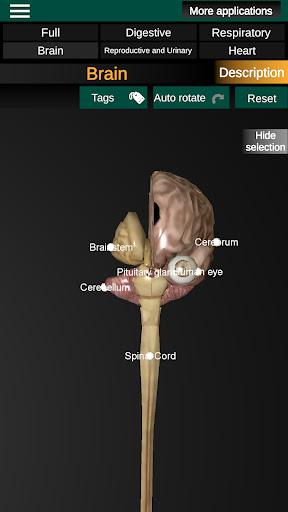

* Hersenen, waaronder de hersenen, het cerebellum en de hersenstam vallen.

* Gemakkelijk te openen en te navigeren (zoom, 3D-rotatie).

* Verberg of toon informatie.

* Beschrijvingen van elk orgel.